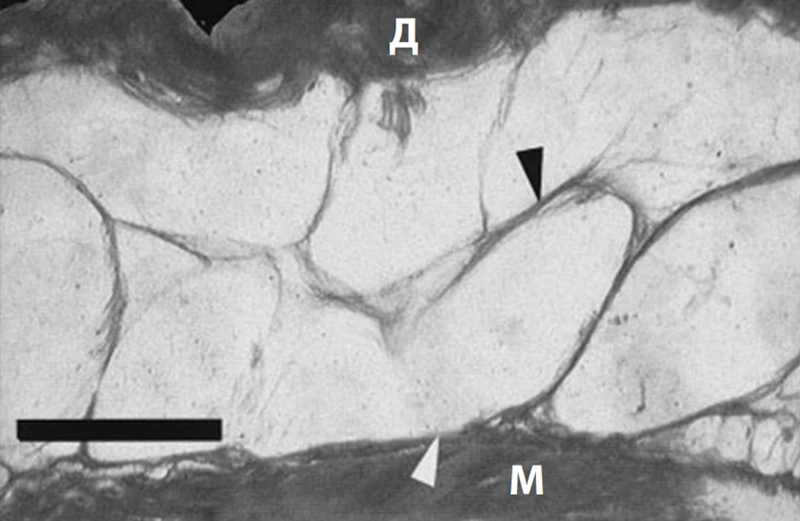

• жировой слой и дерма (образуют фибросептальную сеть, которая разделяет жировую ткань на дольки и затем крепится к дерме, формируя связки кожи retinaculum cutis; RC). RC защищают кожу от гравитации и растяжения, а также сохраняют трехмерную волокнистую структуру (рис. 2)3. С возрастом происходит уменьшение площади и толщины RC, параллельно усугубляется дряблость кожи (рис. 3, 4)4, 5.

Рис. 2. Кожные связки (retinaculum cutis; RC) / фибросептальная сеть жировой ткани (ФСС) передней поверхности предплечья. Белые стрелки – глубокая фасция, черные – RC. М – мышца; Д – дерма3.